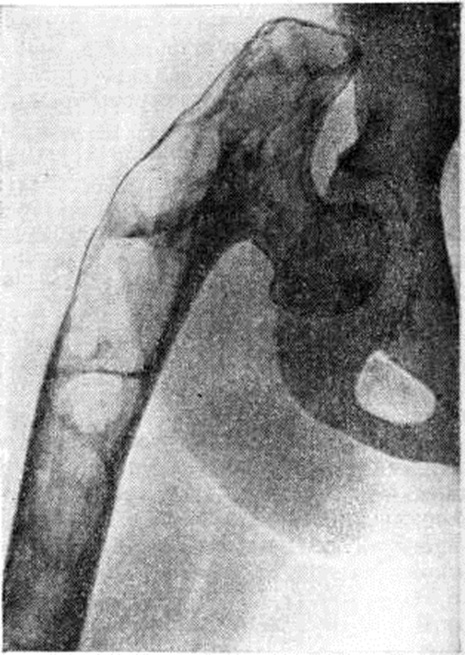

При диффузной форме Фиброзная остеодисплазия поражается вся толща кости. Нередко определяются различные угловые и дугообразные деформации костей. Наиболее часто выявляют варусную деформацию шейки бедренной кости (рисунок 4), варусную или вальгусную деформацию в коленном суставе. В местах наибольшего напряжения искривлённых костей могут определяться зоны дистрофической перестройки (смотри полный свод знаний: Лоозера зоны) и патологический переломы.